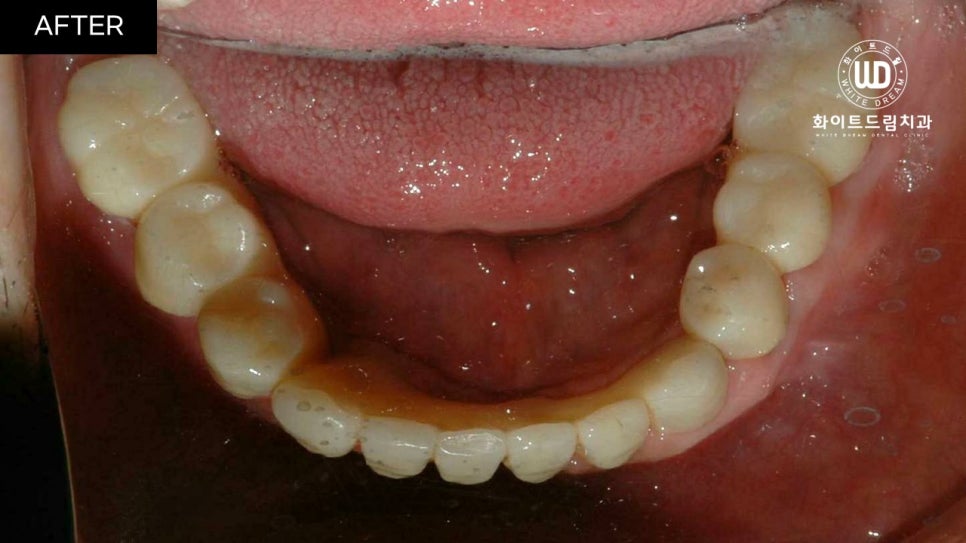

중간 지주대를 픽스처에 연결해주고 2주뒤 최종 보철물까지 올려주니 실제 치아와 비슷하게 기능적, 심미적으로 회복되었습니다.

진행한 치료 기간은 22년 6월부터 22년 12월까지 약 6개월 정도 소요되었습니다.

상악 2번 하악 1번 총 3번에 걸쳐 상악동 거상술과 뼈이식을 동반한 임플란트 식립을 진행했습니다. 그 후, 5개월 뒤 임플란트 보철 인상채득 후 2주 뒤에 보철을 마무리 해드렸습니다.

치아 정면 전/후 사진을 함께 살펴보면, 임플란트 식립 모양이 돔 형태로 예쁘게 이식된 것을 확인할 수 있습니다. 전체 임플란트는 교합면을 잘 선정하는 것이 중요합니다. 교합면은 자연치가 맞물리는 면으로, 너무 높으면 턱관절에 무리가 갈 수 있고 저작할 때 고르게 분산되지 않습니다.

반대로 너무 낮으면 구강 내부 혀나 볼을 씹어 상처가 나고, 턱 모양에도 영향을 끼칠 수 있기 때문에 정밀 검사 후 적절하게 식립하는 것이 좋습니다.

환자분께서 아직 젊은 나이임에도 불구하고 좋지 않은 치아상태로 인하여 자신감이 많이 하락하신 상태였는데, 씹는 힘은 물론 외적인 모습까지 복구가 되어 만족스러운 결과를 얻으셨습니다.

전체발치 및 전체 임플란트 식립은 사후관리가 필수인데, 현재까지 큰 불편함 없이 잘 사용하고 있다고 하셨으며, 정기적으로 검진 또한 잊지 않고 관리해주고 계십니다.